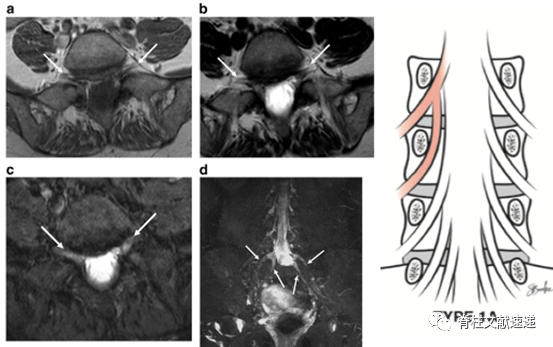

2.MR神经成像(MR neurography imaging)能够更清楚的显示异常神经根。

MR神经成像与术中对照。异常神经根为Neidre分型IA型,从上位神经根发出,然后与硬膜平行向下走形,从下一个椎弓根下穿出。

文献报道通过仔细阅MRI,神经根变异术前发现率约为40%。这就需要临床医生在阅片时格外认真,必要时行MR神经成像。但是,还有60%是术前不易发现的,这就需要每一台手术都要充满敬畏,不可大意。良好的无血术野、充分的照明和放大、谨慎的使用尖刀和钳子,能够降低神经根损伤的发生。